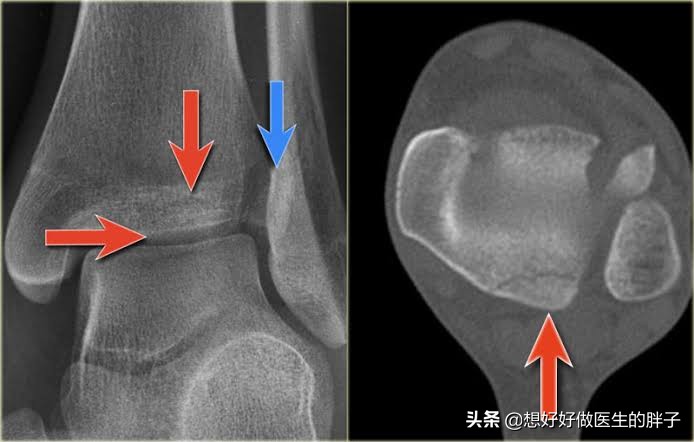

腓骨远端的螺旋骨折

在踝关节的损伤当中,有一种情况叫螺旋骨折,这种骨折在踝关节扭伤当中非常的常见。在损伤当时拍x线的时候,通常情况下骨折离断的并不是特别的明显,整体形态看着还可以,所以很多人采取了保守治疗。但是x线检查通常是平面的检查,它并不能代替整个三维情况的表现,一些螺旋骨折的患者往往需要进行手术治疗,因为这种骨折不是属于稳定骨折,很有可能保守治疗效果不好,骨折断裂的距离会越来越大。

如果是这种情况导致三个月的时间踝关节还疼,应该复查x线,明确骨折恢复的情况,此时已经错过了最佳的治疗时间,如果强行手术将已经形成骨痂的部分重新打开,将会造成比较大的创伤。所以如果不是情非得已还是要考虑进行保守治疗,如果疼痛比较明显,可以口服或者是外用一些镇痛药物帮助控制疼痛,要加强踝关节的康复锻炼。尽量的减少长时间的负重行走,给踝关节一个恢复的机会,有的时候症状慢慢的就会消失掉。